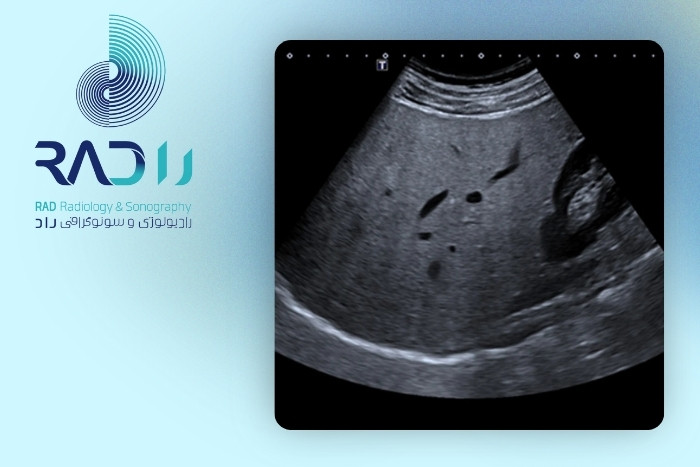

علت پنهان ماندن تودههای کبدی در سونوگرافی

سونوگرافی یکی از اولین و رایجترین روشهای بررسی کبد است؛ اما همیشه قادر به نمایش تمام تودهها نیست. علت پنهان ماندن تودههای کبدی در سونوگرافی مجموعهای از عوامل بالینی، تکنیکی و ویژگیهای خودِ توده است. مهمترین دلایل عبارتاند از:

در مجموع سونوگرافی روش بسیار خوبی برای ارزیابی کبد است اما محدودیتهایی دارد. اگر پزشک شک بالینی داشته باشد معمولاً از روشهای دیگر برای تشخیص دقیقتر استفاده میکند.